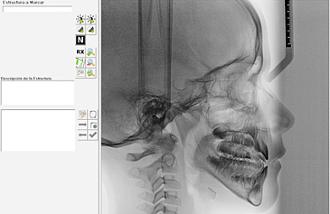

Es una radiografía lateral del cráneo. En una cefalometría podemos realizar un análisis de los tejidos blandos, esqueleto facial y tejido dentario.

Los estudios cefalométricos o cefalometrías se emplean para los estudios y planificaciones de tratamientos de ortodoncia. Tienen como objetivo obtener medidas del cráneo y compararlas con patrones estándar evaluando y analizando la relación entre los huesos del cráneo, la mandíbula y los dientes, así como el crecimiento facial y las anomalías esqueléticas.